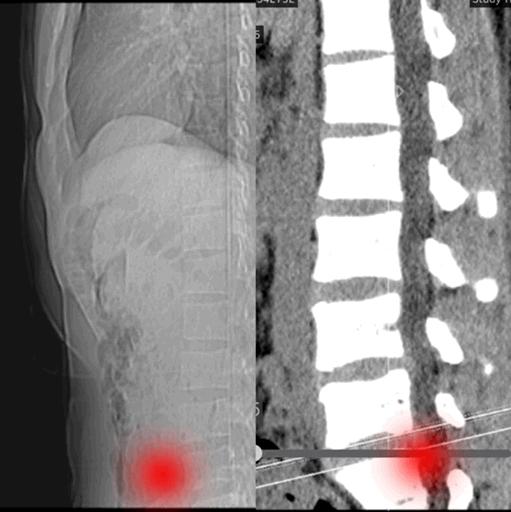

我们看一下下腰的时候,脊柱在x光下发生了什么事情。正常的生理曲度就是这样被掰直的

胸椎变直,人会相当的挺拔,这就是舞蹈中要求的挺胸。

挺拔的后背谁能拒绝?但是腰椎曲度就是这样被生生掰直的。

这时候你的颈椎、胸椎、腰椎已经完全贴合了墙壁。获得一个挺拔优美的体态,但是所有的生理曲度都没了。

曲度消失就意味着脊柱的减震缓冲功能消失了。正常的生理曲度会帮助我们抵消掉日常坐、立、行走、负重对椎间盘的压力。保护髓核,脊神经等重重要组织。

生理曲度消失以后呢,脊柱被直接碾压,外界的力直接压在脊柱上。这就是为什么腰椎曲度变直的人,腰五骶一是最容易突出的原因。